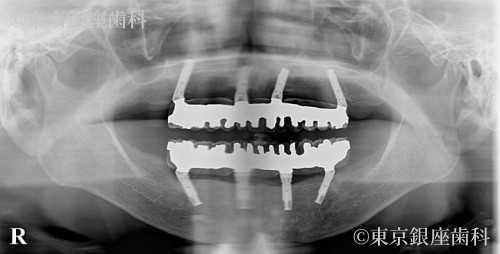

20年経過したインプラントの上部構造を再度新製し快適性を取り戻した80歳代女性の症例

After

20年前にワンデイインプラントを実施。土台は安定していたが人工歯が経年劣化し再度新製を選択。スペアも作成し将来の負担を軽減した。

上下ワンデイインプラント(補綴再製作)